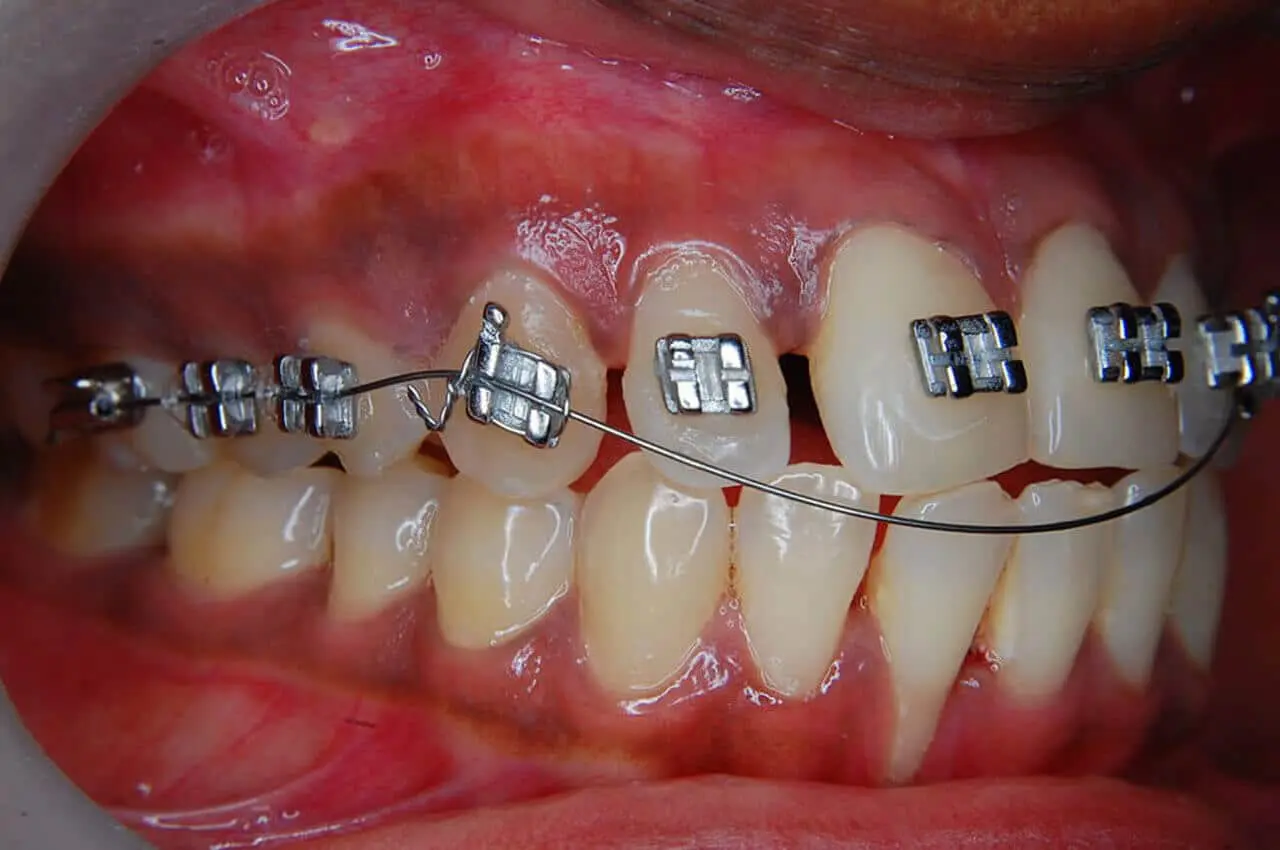

Inoltre, l’apparecchio fisso offre una precisione maggiore nel movimento dei denti, poiché ogni bracket (la placchetta fissata sui denti) è connesso al filo metallico che esercita una pressione costante, facendo sì che i denti si spostino nella direzione desiderata.

Un altro svantaggio significativo dell’apparecchio fisso è la difficoltà nell’effettuare una corretta igiene orale. I fili e i brackets possono intrappolare il cibo e la placca, aumentando il rischio di carie e infiammazione gengivale. È quindi fondamentale fare attenzione a come si puliscono i denti durante il trattamento. Ecco alcuni dei problemi comuni:

- Accumulo di placca: se non si puliscono accuratamente, i residui di cibo e placca possono accumularsi attorno ai brackets, provocando carie o gengiviti.